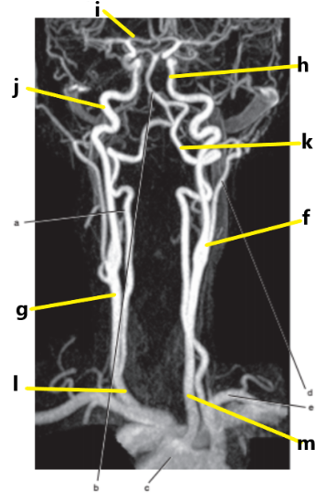

What is letter l ?

Common carotid

What is letter e ?

Subclavian artery

What is letter f ?

Common carotid artery

What is letter i ?

Anterior cerebral artery

What is letter m ?

What is letter j ?

Internal carotid artery

What is letter g ?

Vertebral artery

Aortic arch

What is letter b ?

What is letter k ?